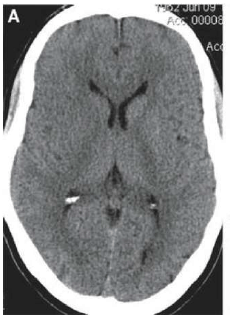

Paciente do sexo masculino, 60 anos, admitido em departamento de emergência com quadro insidioso e progressivo de redução de força e sensibilidade no hemicorpo esquerdo há mais ou menos 2,5 horas. Tem antecedente de hipertensão arterial e dislipidemia há mais de 20 anos, em tratamento irregular com losartam, hidroclorotiazida e atorvastatina. Ex-tabagista. Ao exame físico, paciente com abertura ocular a estímulos verbais, contactuante e obedecendo comandos simples. Apresenta hemiparesia e hipoestesia em hemicorpo esquerdo. Ritmo cardíaco regular, frequência cardíaca 90bpm, pressão arterial em membros superiores e inferiores (deitado) 190x100mmHg, frequência respiratória 19ipm, SpO2 88%. Tomografia de crânio evidenciou o resultado a seguir.

A conduta, nesse momento, em relação à pressão arterial do paciente relatado no Quadro Clínico 1 é

A principal hipótese diagnóstica é de acidente vascular encefálico